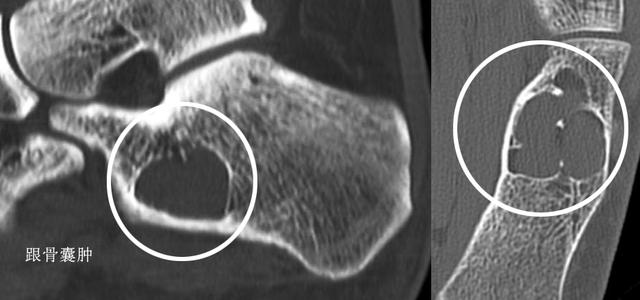

跟骨囊肿诱发的跟痛

说到这个疾病谢医生是感到非常愧疚的,因为在这个疾病上吃过亏。

十余年前有一个朋友的孩子因为跟痛找到了我,当时经验还是比较浅薄,查体之后简单判断了是由于跑跳诱发的跟腱炎,未给与重视。后来一周后疼痛加重,检查X光才发现是跟骨囊肿,还好并未影响孩子的治疗,否则后果不敢想象。

所谓吃一堑长一智,也是从那以后我都会建议跟痛的患者做一个X光检查, 排除囊肿和骨破坏的可能。

小的囊肿一般不会有任何症状,但是如果囊肿较大,产生了疼痛症状,建议手术切除囊肿给与植骨的手术治疗,否则随时有跟骨骨折的风险。